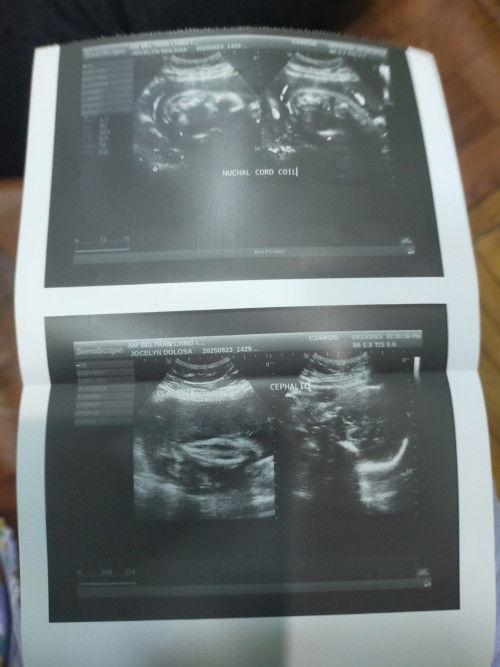

Normal or delikado ba ang nuchal Cord Coil ?

Normal poba or Delikado ito

it can happen. delikado if tight na nakapulupot ang cord sa leeg ni baby. lalo na kapag hindi makalabas si baby thru vaginal birth. CS is done. if loose at tingin ng OB its possible na vaginal delivery, pwede. always pray.

Anong ultrasound to mi?